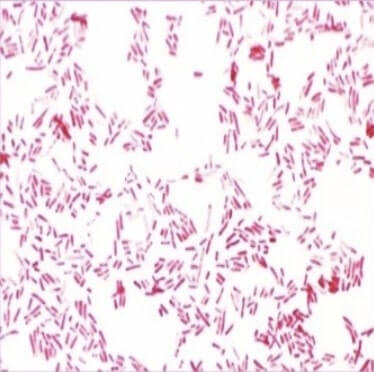

Ectolysins Against Gram Positive and Gram Negative Bacteria